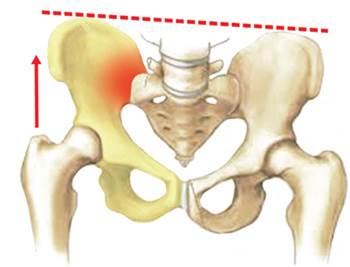

Sacroilitis (inflamació de l’articulació sacroilíaca) dreta a causa

d’una dismetria amb inclinació pèlvica cap a l’esquerra

La sacroilitis és la inflamació de l’articulació sacroilíaca i pot tenir moltes causes. La majoria de sacroilitis són causades per una sobrecàrrega de l’articulació, sigui per un excés de rigidesa de la columna lumbar (per exemple després d’una artròdesi instrumentada amb fixació dels discs intervertebrals, etc.), per una dismetria (diferència de longitud de les dues cames que provoquen una inclinació pèlvica i una sobrecàrrega d’un dels costats), etc.